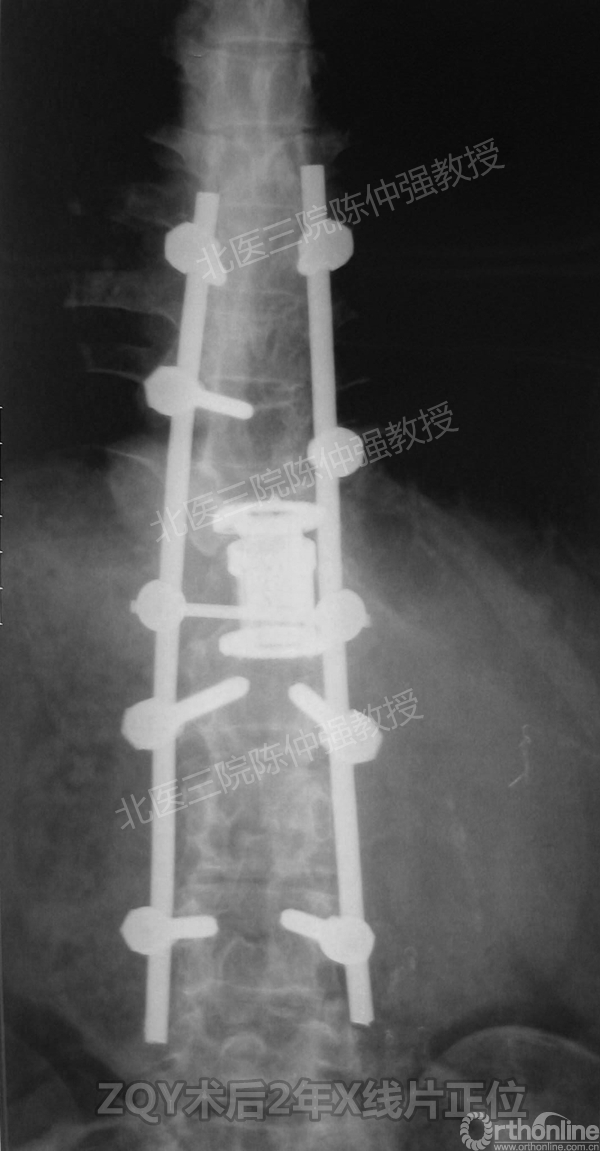

2005年,陈仲强教授在AOSpine年会上分享了一例胸腰椎陈旧结核性侧后凸畸形病例。资料如下:

ZQY术后2年

患者女性17岁,胸腰椎陈旧结核性侧后凸畸形,局部呈“麻花状”扭转,无神经功能受损表现。2005年,陈仲强教授带领团队实施后路+侧前方联合入路脊柱节段切除、双轴旋转矫形术。术后患者外观显著改善,神经功能正常。术后随访证实患者截骨矫形节段骨性融合良好,矫形效果持续良好。